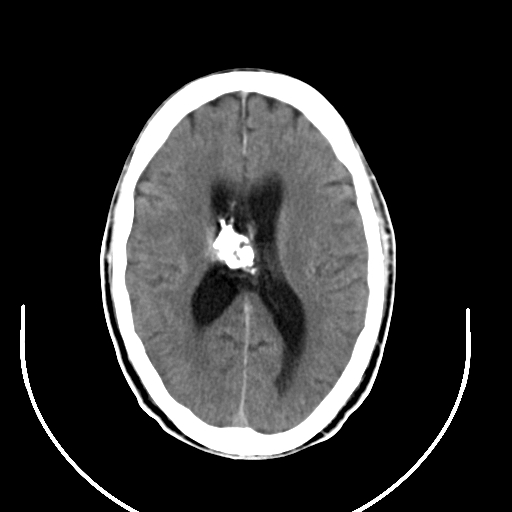

以下是引用拾荒者在2008-7-26 15:36:00的发言:[br]侧脑室内高密度钙化影,未见软组织结构,侧脑室未见增大,考虑良性钙化性改变(钙化型脑膜瘤可能)。

以下是引用宇宙ct在2008-7-26 13:43:00的发言:[br]支持:钙化性脑膜瘤。 不排除脉络膜瘤 [br] [br]